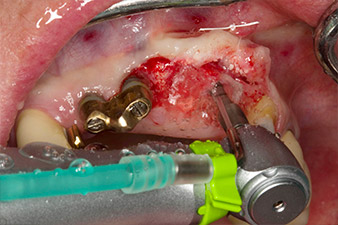

Following primary healing, the soft tissues were shaped using the basally lined bridge. Two months later the site was exposed by a slightly palatal alveolar ridge incision (Fig 2). The dimensions of the alveolar bone proved to be sufficient at position 22. Figures 2 and 4 show the preparation of the implant bed, the tapping and the implantation using Implantmed.

The new implantology motor was used with the appropriate W&H surgical contra-angle handpieces.

In order to compensate for the periodontal bone loss and achieve an aesthetically pleasing result, the implantation was combined with guided bone regeneration (GBR) with xenogenic replacement material and a collagen membrane

(Fig. 5 and 6).